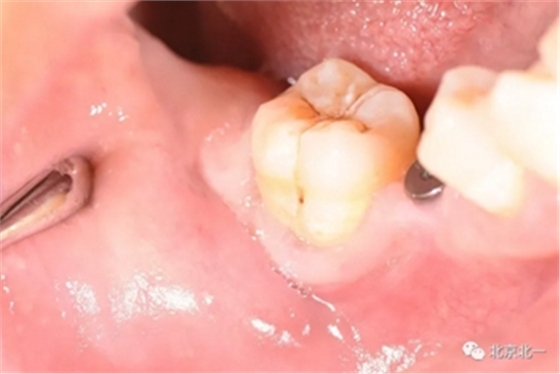

第一步:术中微创种植, 穿龈愈合。

第二步:拔牙